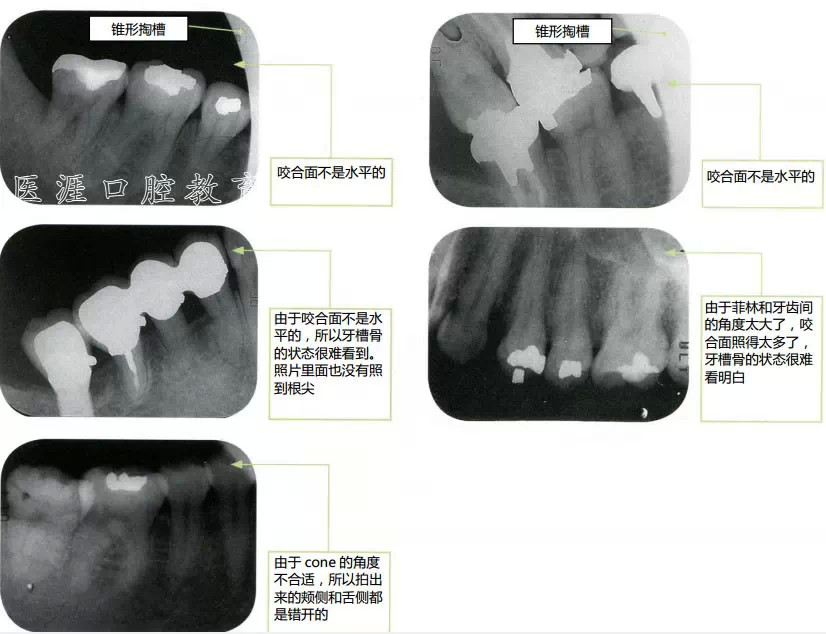

什么是不好的X光片1(14張法)

什么是不好的X光片2

cone的位置與想要拍攝的牙齒的位置錯(cuò)開了